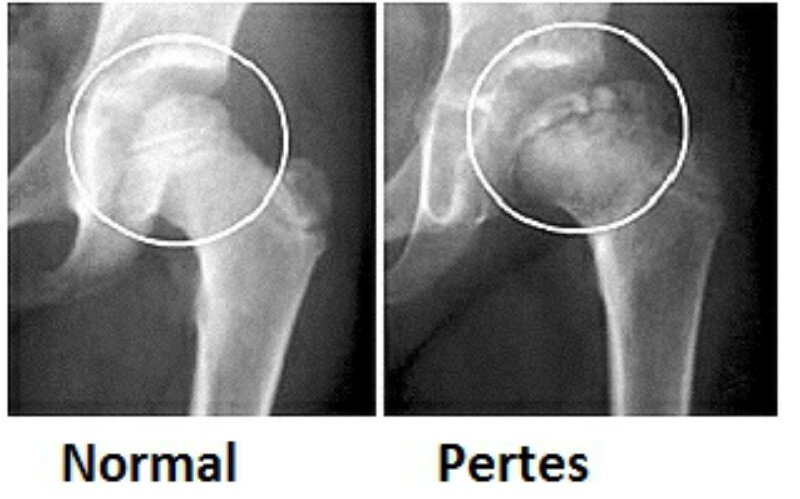

O que é a Doença de Perthes e como ela afeta o quadril infantil?

A Doença de Perthes, também chamada de Doença de Legg-Calvé-Perthes, é uma condição ortopédica que afeta o quadril de crianças.

Ela acontece quando o fluxo sanguíneo para a cabeça do fêmur diminui ou é interrompido temporariamente.

Isso faz com que o osso da cabeça do fêmur perca nutrientes, fique mais frágil e comece a se deformar com o tempo.

Como a Doença de Perthes afeta o quadril?

Com a diminuição do fluxo sanguíneo, a cabeça do fêmur começa a perder a sua forma arredondada.

Essa deformidade pode prejudicar o encaixe do fêmur na articulação do quadril, causando: